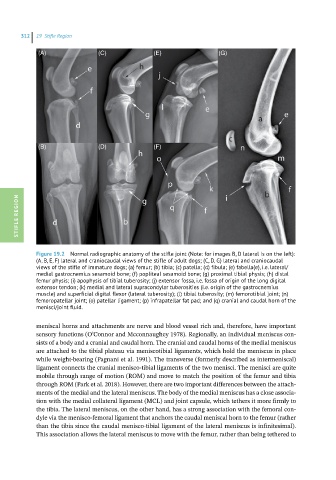

Figure 19.2 Normal radiographic anatomy of the stifle joint (Note: for images B, D lateral is on the left):

(A, B, E, F) lateral and craniocaudal views of the stifle of adult dogs; (C, D, G) lateral and craniocaudal

views of the stifle of immature dogs; (a) femur; (b) tibia; (c) patella; (d) fibula; (e) fabella(e), i.e. lateral/

medial gastrocnemius sesamoid bone; (f) popliteal sesamoid bone; (g) proximal tibial physis; (h) distal

femur physis; (i) apophysis of tibial tuberosity; (j) extensor fossa, i.e. fossa of origin of the long digital

extensor tendon; (k) medial and lateral supracondylar tuberosities (i.e. origin of the gastrocnemius

muscle) and superficial digital flexor (lateral tuberosity); (l) tibial tuberosity; (m) femorotibial joint; (n)

femoropatellar joint; (o) patellar ligament; (p) infrapatellar fat pad; and (q) cranial and caudal horn of the

menisci/joint fluid.